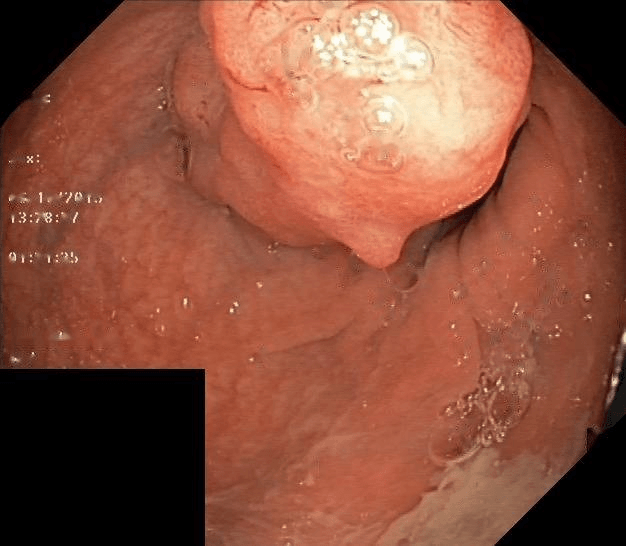

First, it is necessary to convert the image from the original RGB channel to grey scale to process the subsequent procedure. Rather than adaptive thresholding, the proposed approach employs standard thresholding method with a fixed threshold value to identify specular highlights in all images. This is due to the gastrointestinal image’s varied textures and components, and if not done properly, may result in information loss. Some samples of the dataset contain text, high exposure regions and brightly colored instrument, as described in Figure 4. Aside from text in white color, high exposure regions are parts of specular highlights that received excessively high intensity compared to regular highlight spots, while the instruments are sometimes in white or blue color. After thresholding, these factors may emerge in the mask, as shown in Figure 4(b), and affect the inpainting outcome. Thus, the following step is to remove these undesired elements from the mask in order to assure consistency. To cope with these problems, two directions are considered, either to perform segmentation for text, polyp and instrument, separately, or remove the parts that meet certain size threshold. For simplicity, the second approach is used in this study.

Refer to caption

(a) Original image

(b) Thresholding

(c) Detection of undesired regions

(d) Preprocessed mask

Figure 4: An illustration of specular highlights detection from a colonoscopy image that contains text, high exposure regions and a white instrument.